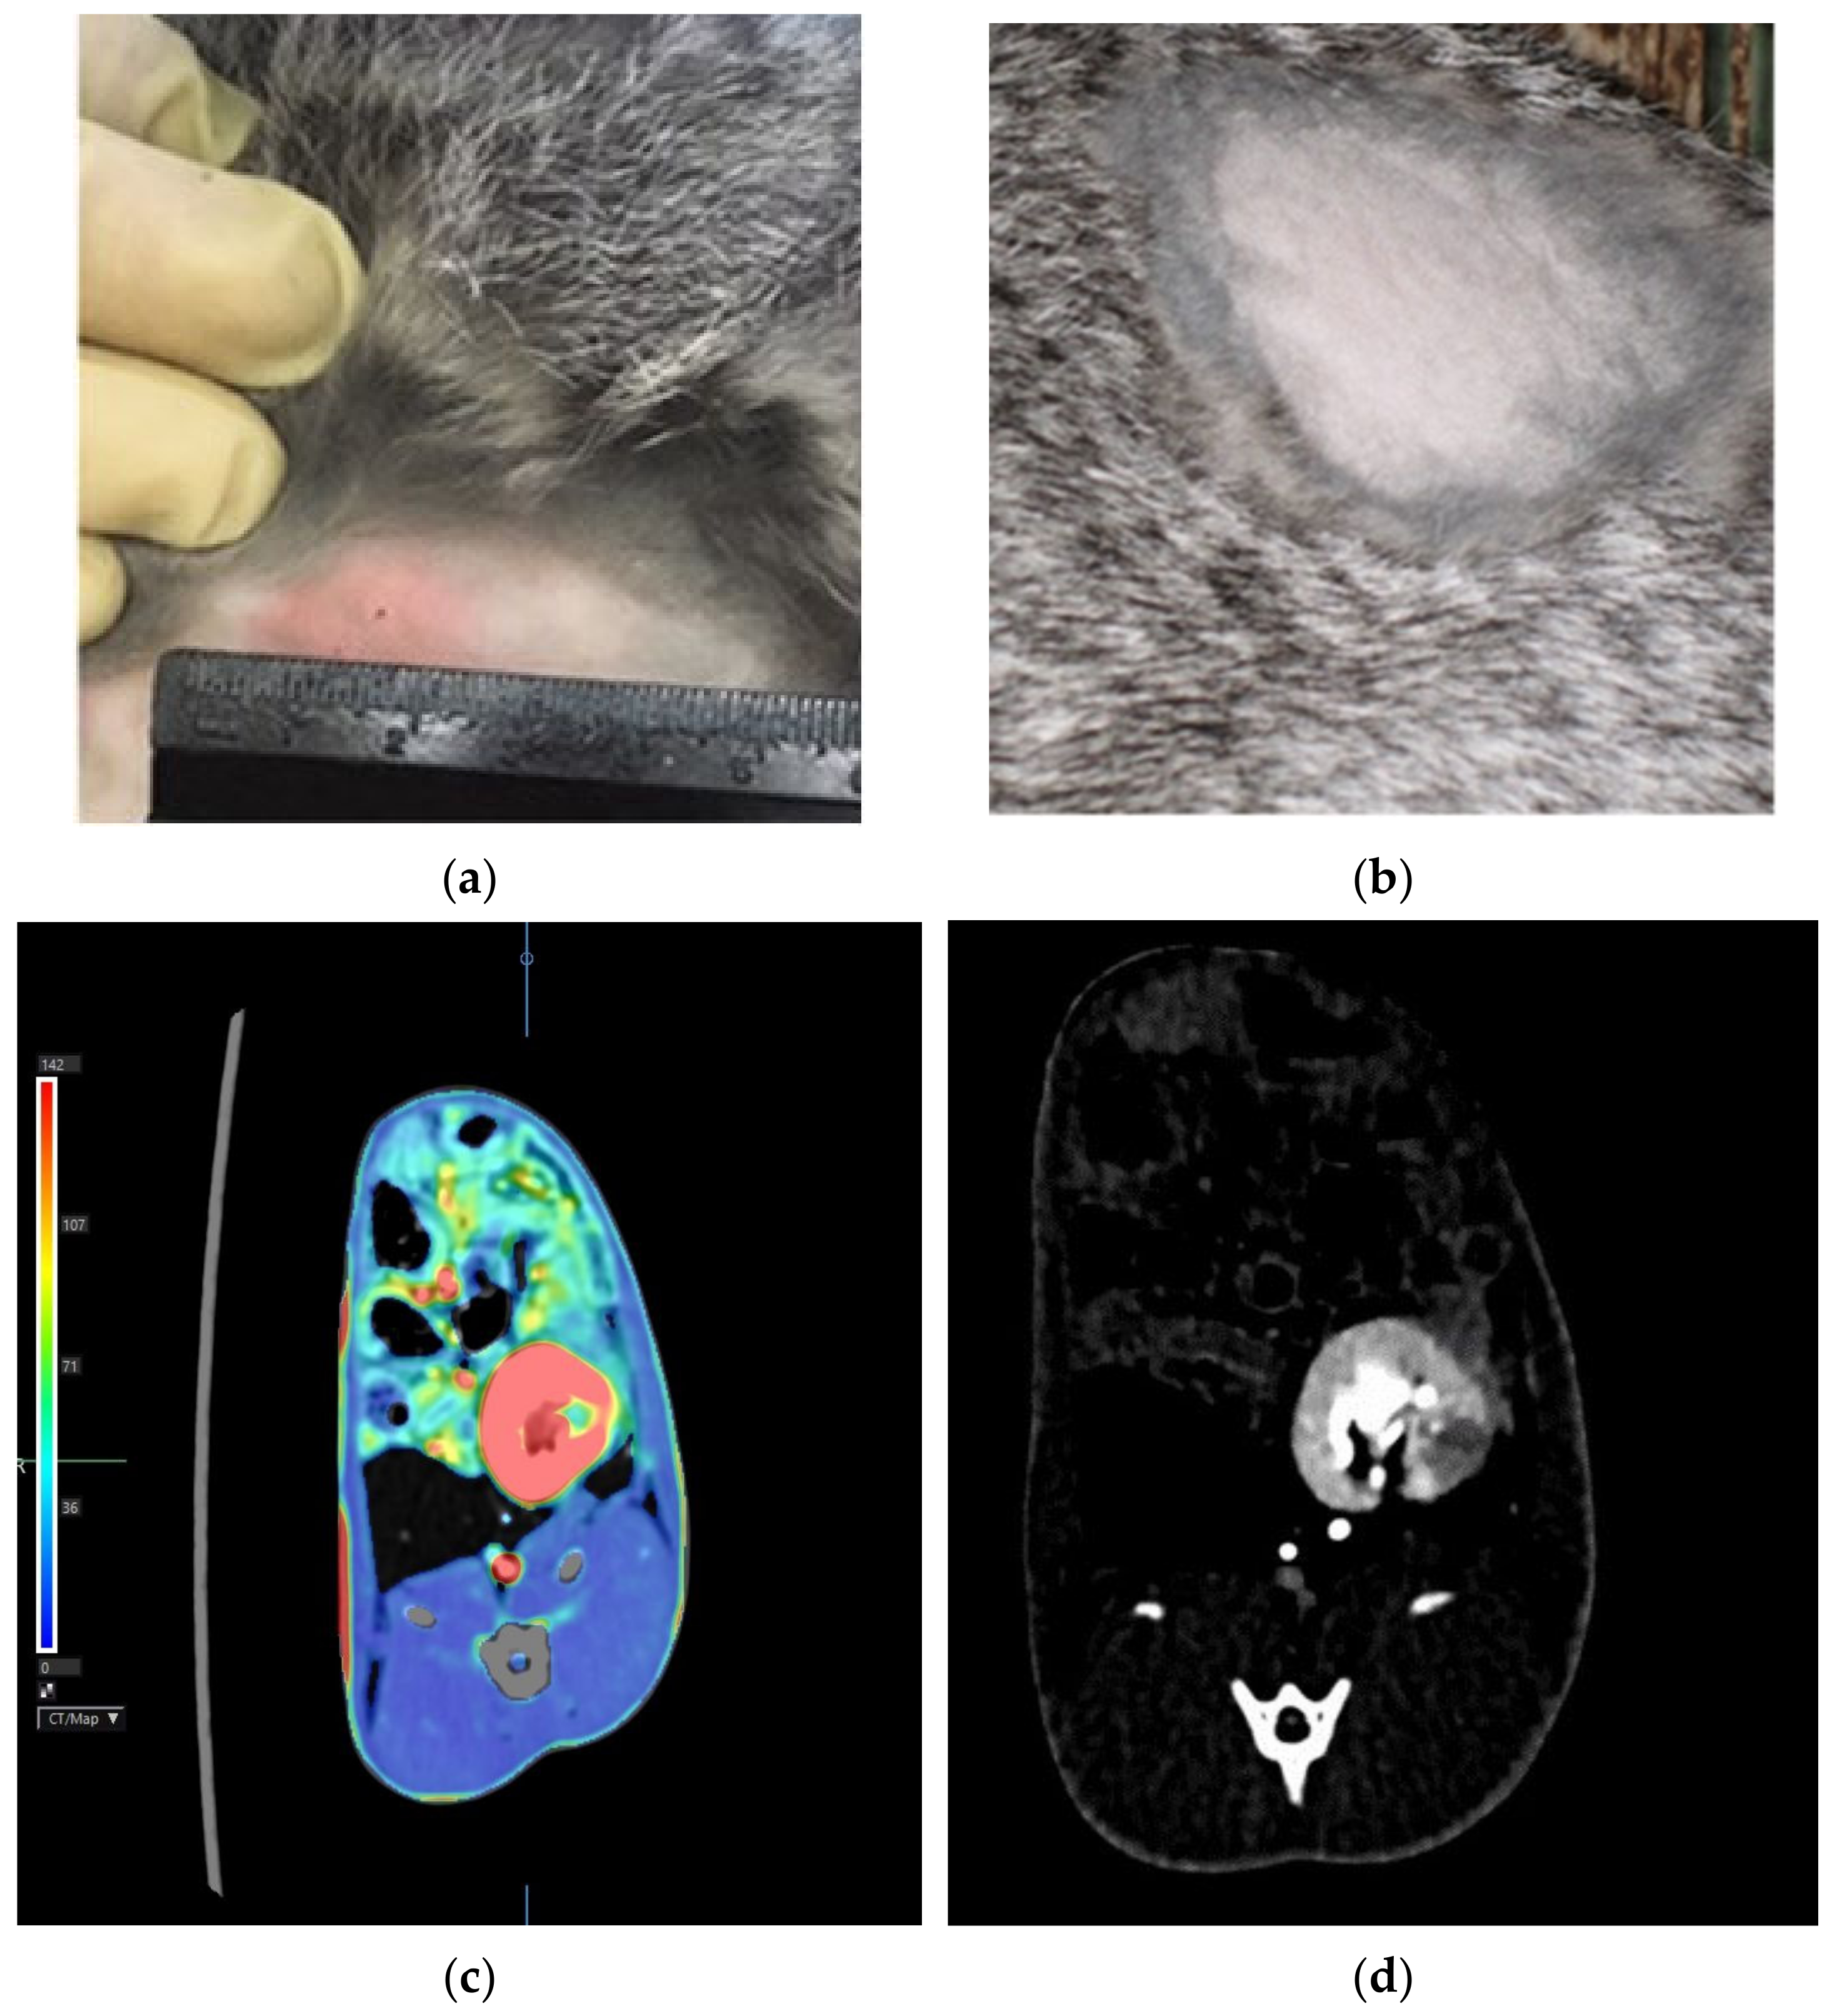

- Yudintceva, N.; Mikhailova, N.; Bobkov, D.; Yakovleva, L.; Nikolaev, B.; Krasavina, D.; Muraviov, A.; Vinogradova, T.; Yablonskiy, P.; Samusenko, I.; et al. Evaluation of the biodistribution of mesenchymal stem cells in a pre-clinical renal tuberculosis model by non-linear magnetic response measurements. Front. Phys. 2021, 9, 625622. [Google Scholar] [CrossRef]

- Yudintceva, N.M.; Bogolyubova, I.O.; Muraviov, A.N.; Sheykhov, M.G.; Vinogradova, T.I.; Sokolovich, E.G.; Shevtsov, M.A. Application of the allogenic mesenchymal stem cells in the therapy of the bladder tuberculosis. J. Tissue Eng. Regen. Med. 2018, 12, e1580–e1593. [Google Scholar] [CrossRef]